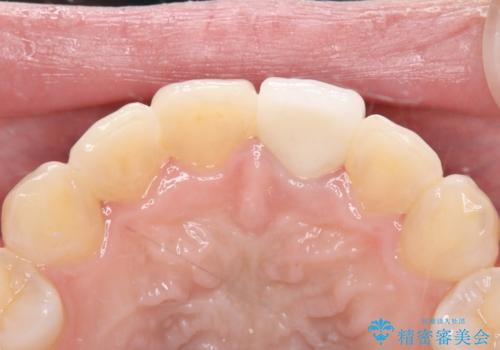

オールセラミッククラウンによる修復: 最終的な被せ物には、一切の金属を使用しないオールセラミックを選択。隣の天然歯と色調や透明感を精密に合わせることで、どこを治療したかわからないほど自然な仕上がりとなりました。